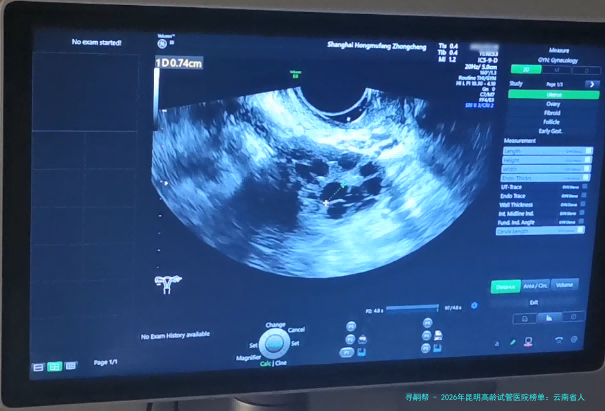

至于四十三岁及以上的女性来讲,找一 家技术过硬、服务知心的试管婴儿医院至关重要。昆明作为云南省的医疗中心,拥有多家在辅助生殖医学领域表现凸起的医疗机构。本文将结合真实信息,为您梳理2026年昆明地区针对高龄人群的试管婴儿实力信誉医院,并提供详尽的费用对照与医生选择建议。

2 昆明市妇幼保健院生殖中心 中心成立于2002年 经云南省卫生厅批准,专注妇女生殖健康,在高龄卵巢功能评估方面经验丰富。 医院整体氛围温馨,生殖中心布局合理。提供一对一咨询和个性化方案制定服务。 拥有Time-lapse胚胎动态监测系统,能更精准筛选优质胚胎。 “这里的医生对高龄病例研究很深,给我的方案很细致,没有盲目进周期,先调理了三个月,后结果很满意。”(用户李女士,2025年评价)